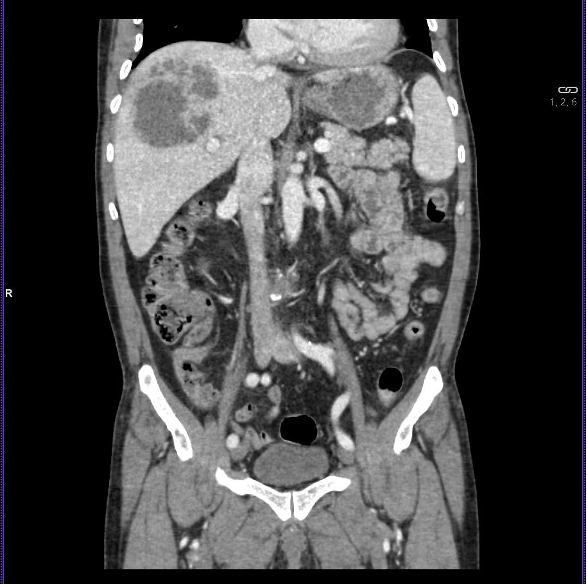

TC abdominal con contraste IV